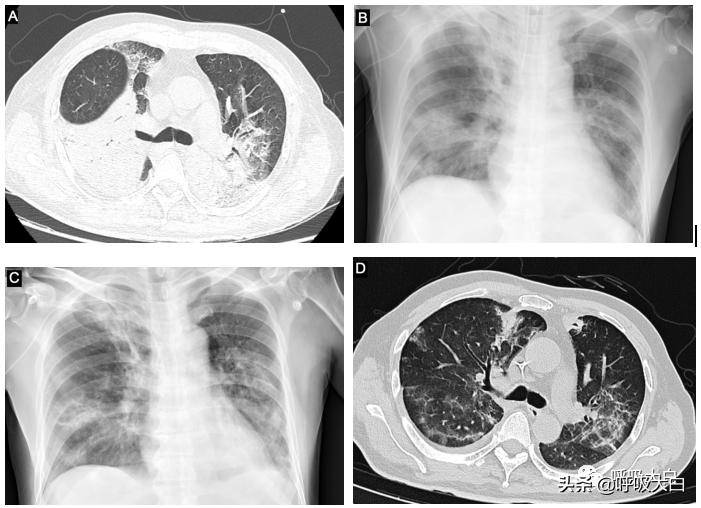

病例2 男,55岁,因“发热6d,咳嗽咳痰5d,加重伴呼吸困难1d”入院。患者入院前6d出现发热,最高体温39.3℃,5d前出现咳嗽咳黄脓痰,1d前出现呼吸急促、嗜睡,转入我院。患者既往体健。入院查体:T37.4℃,R25次/min,BP164/87mmHg,HR97次/min,储氧面罩给氧(15L/min)时氧饱和度为88%;两肺呼吸音粗,两下肺闻及散在湿啰音。胸部CT:两肺大片肺炎、实变。血常规:WBC 32.2x10^9/L,N 98.0%,PCT:0.42ng/ml;hs-CRP:334.9mg/L;血气分析:PH值7.48,氧分压58mmHg,二氧化碳分压35mmHg,P/F 96mmHg。

立即予以气管插管下呼吸机辅助通气,给予亚胺培南西司他丁针0.5g q6h联合阿奇霉素针0.5g qd、利奈唑胺0.6g q12h抗感染。第2日床边行肺泡灌洗液送检NGS。3日后提示为鹦鹉热衣原体,患者未能明确有鹦鹉等鸟类禽类接触史。调整抗感染方案为左氧氟沙星针0.5g qd及多西环素胶囊0.1g q12h鼻饲联合哌拉西林他唑巴坦针4.5g q8h。更改抗感染方案6日后体温正常,复查血指标及胸片有好转。患者入院及复查见图2:A入院时,BC治疗期间,D出院时。

图2